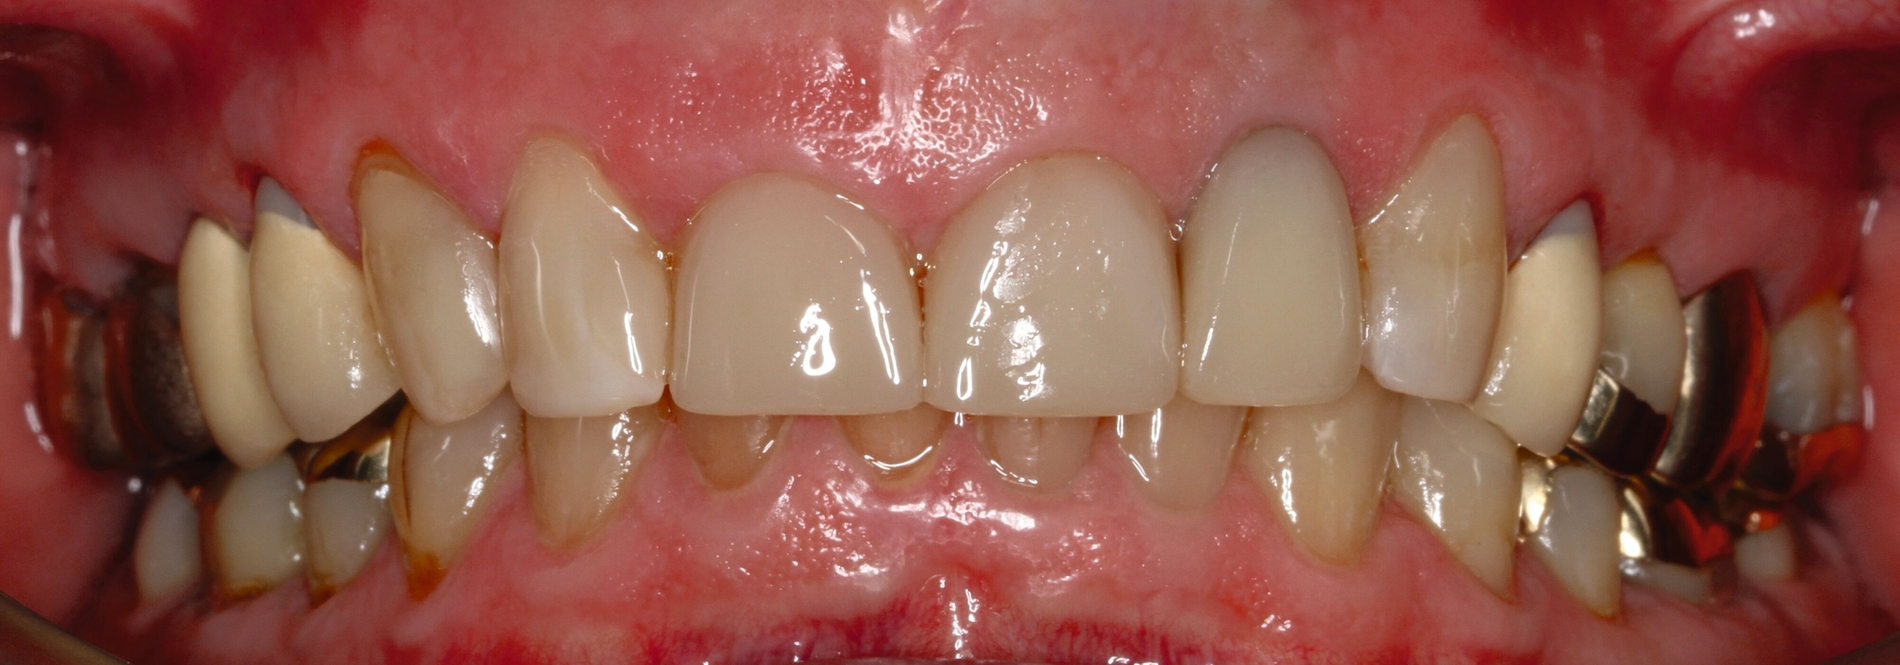

Die dentale Ausgangssituation zeigte im Seitenzahnbereich ein suffizient konservierend und prothetisch versorgtes Gebiss der zweiten Dentition sowie im Frontzahnbereich nicht kariogene Zahnhartsubstanzverluste und eine defekte Krone mit Sekundärkaries (Abbildungen 1 und 2).

Zur Verbesserung der Ästhetik und des Wohlbefindens des Patienten standen die Harmonisierung der Lachlinie und des Frontzahnbogens sowie Farb- und Formkorrekturen der Oberkieferfrontzähne im Fokus. An den Zähnen 11 und 21 waren Zahnhartsubstanzverluste durch Erosion und Attrition zu erkennen. Zahn 23 hatte ebenfalls einen erosiven Defekt, Zahn 13 eine farblich abweichende Kompositrestauration und die Zähne 14 und 24 wiesen keilförmige Defekte zervikal der Kronenränder auf, die einen suffizienten Randschluss haben (Abbildung 1a).

Die Zähne 11, 21 und 32–42 wiesen aufgrund des Zahnverschleißes stark verkürzte klinische Kronen auf. Durch diese Zahnhartsubstanzverluste sind die genannten Zähne über die Zeit elongiert – gut erkennbar an dem in Richtung Okklusionsebene verschobenen Verlauf des Gingivalsaums –, wodurch sich ein frontaler Tiefbiss und in Protrusion eine verzahnte Frontzahnführung im Schlüssel-Schloss-Prinzip mit veränderter Rot-Weiß-Ästhetik adaptiert haben. Daraus resultiert ein verringertes Platzangebot in statischer und in dynamischer Okklusion (Abbildungen 1b und 1d).